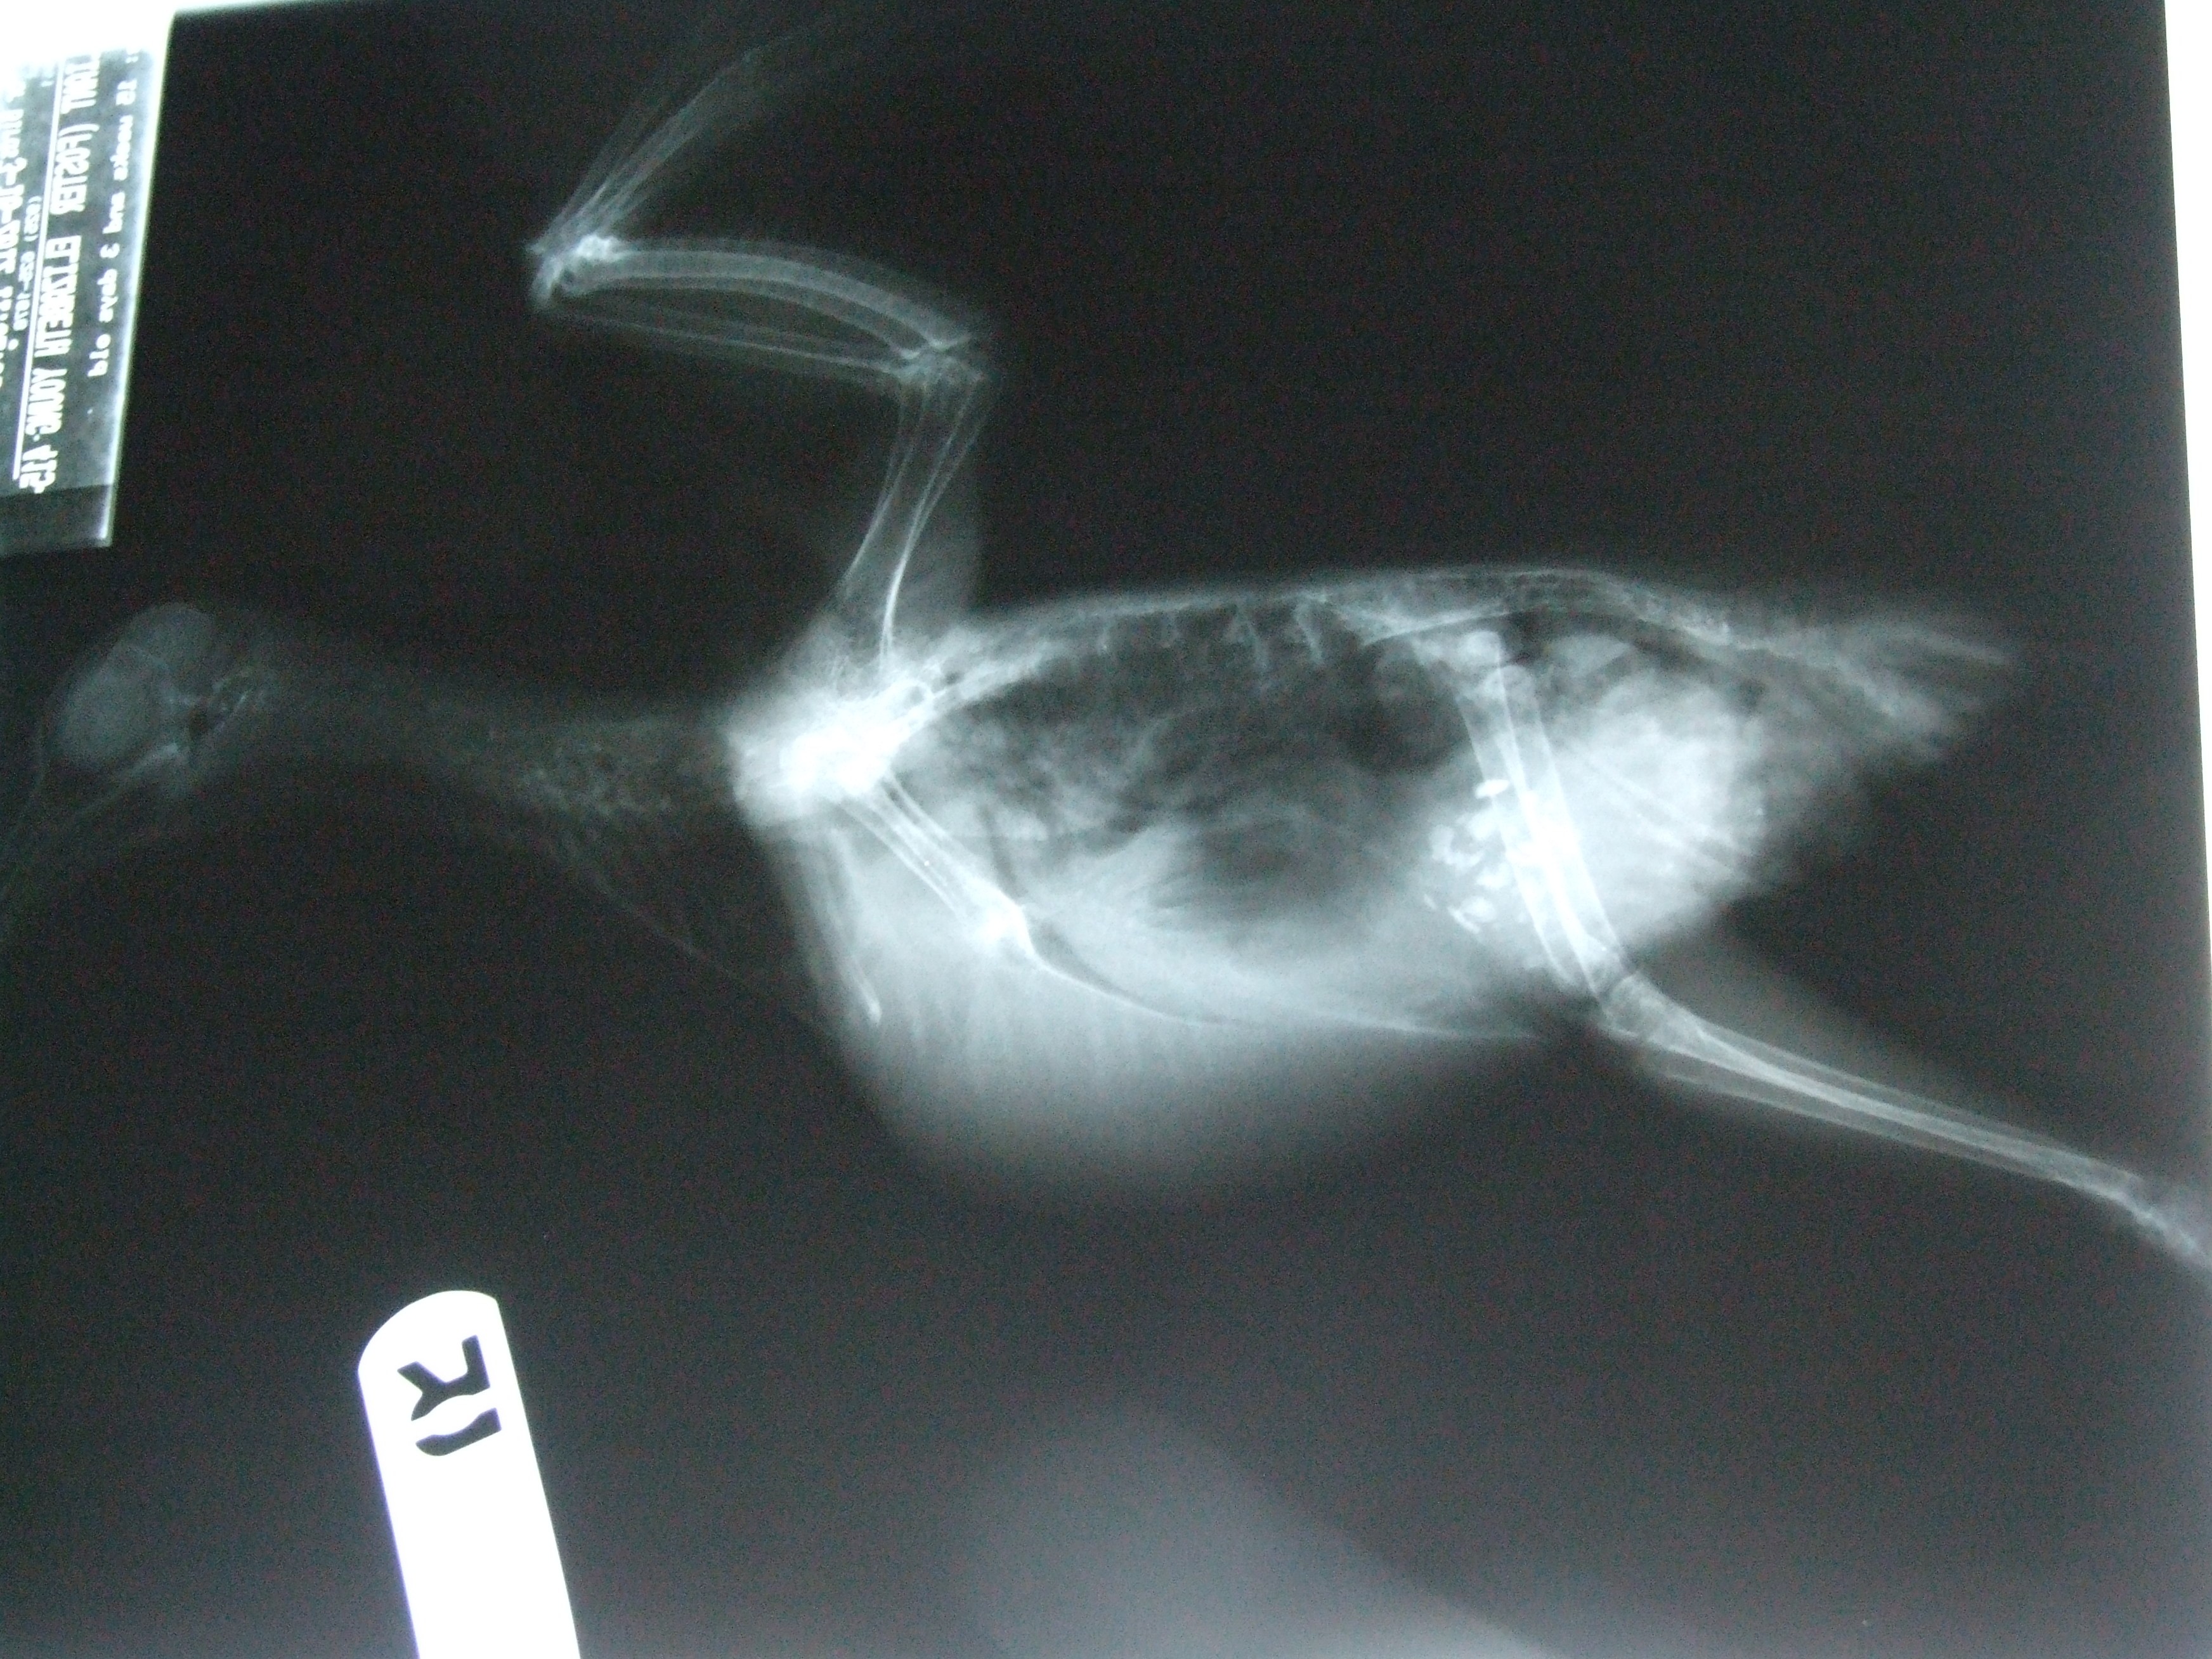

Polka Dot the self-rescuing racer

Last October, an exhausted racing pigeon limped into Laurie’s kitchen through her cat door. Laurie was quite surprised to find him there. But Laurie is an animal lover who rescues cats and has volunteered with wildlife rescue and she knew that this brave little bird needed help. She delivered him to WildCare (who kindly took him in despite his being domestic) but fretted knowing that once he healed up, if not claimed, he’d be transferred to a shelter and perhaps killed for lack of an adopter. Coincidentally, Laurie had just met Linda, one of MickaCoo’s volunteers, and the flock that she fosters in her beautiful backyard aviary. Laurie reached out to Linda and Linda put Laurie and I in touch.